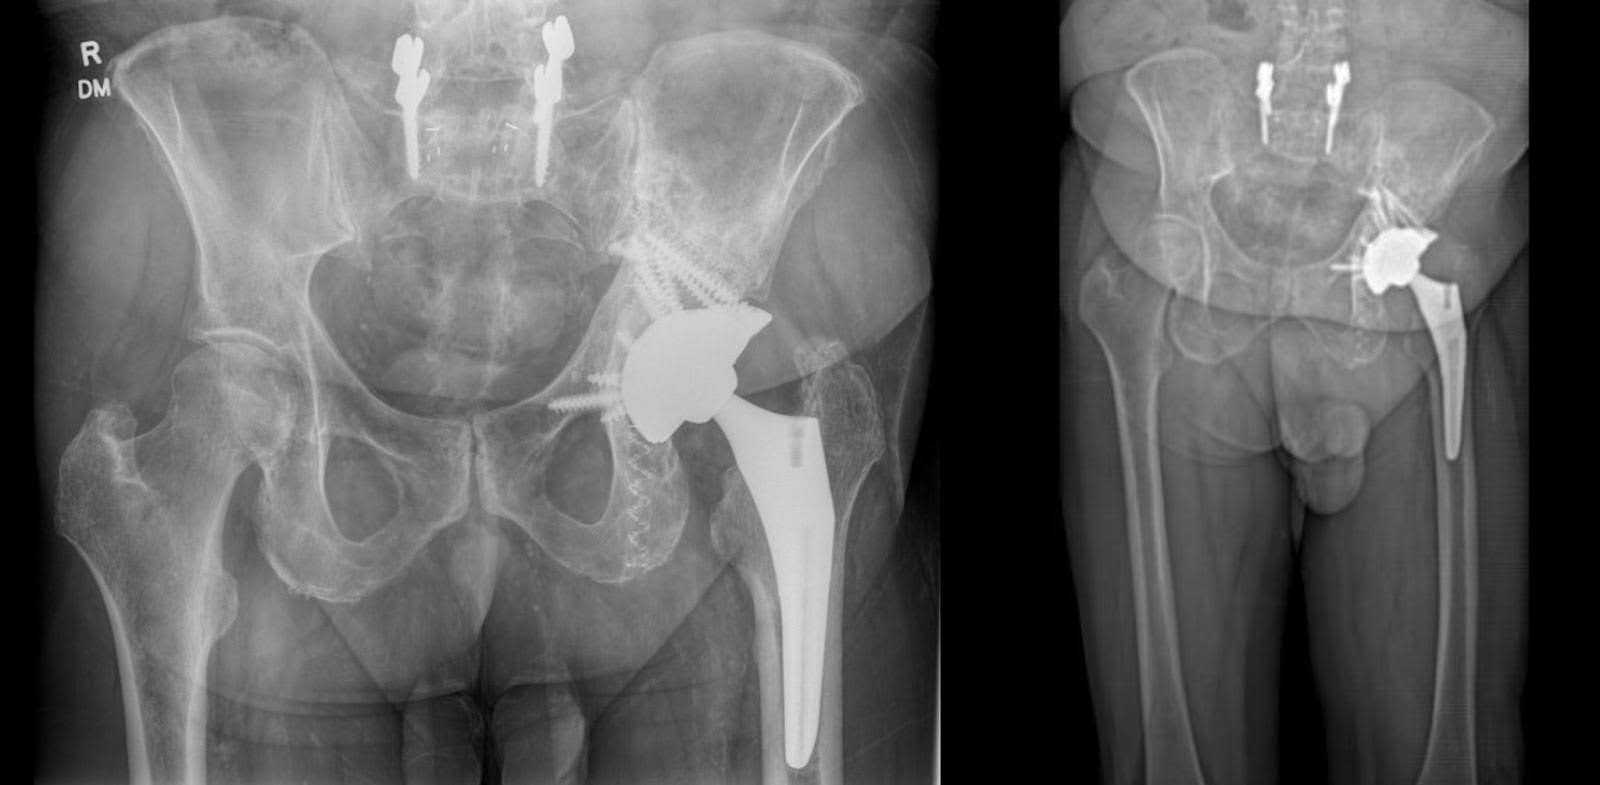

Six months after surgery, the patient demonstrated a full range of motion in the left hip, albeit reporting localized pain during internal rotation. Hip flexion and extension were within normal limits. Clinically, the patient exhibited nearly appropriate leg length, yet displayed an antalgic gait with reduced left stride length compared to the right. Despite participating in over 30 physical therapy sessions, the patient experienced moderate fatigue and pain during ambulation, necessitating frequent breaks after walking moderate distances. Left groin and lateral hip pain still increases during translational and prolonged periods of activity. X-rays of the hip joint and pelvis revealed a well-aligned left THA with tantalum augments in optimal positions, showing no signs of loosening (Figure 5).

Figure 5. AP X-ray of the pelvis six months after surgery. Stable alignment following left total hip arthroplasty with acetabular augmentation, alongside fixation of the left ischial and iliac bone using photodynamic nails. No evidence of periprosthetic fracture.